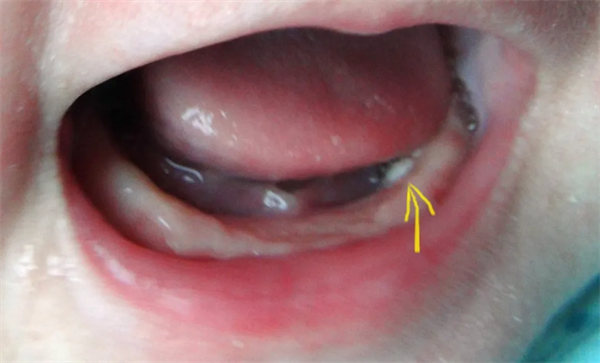

10. 口腔里的“小白點”?是“馬牙”,別挑破!

在寶寶口腔上顎中線或牙齦上,可能看到黃白色、米粒大小的小顆粒,這是“馬牙”,是上皮細胞堆積或黏液腺分泌物潴留形成的,數周后會自然脫落。

重要提醒:絕對不能用牙簽、針去挑破,以免引起口腔感染,甚至導致敗血癥。